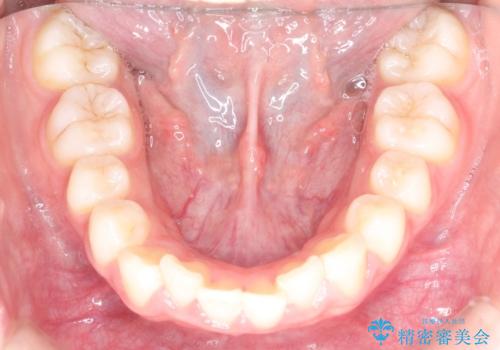

- 前歯の隙間と、出っ歯に見えることを主訴に来院されました。

できるだけ目立たない装置をご希望されましたので、インビザラインにて治療を行いました。

治療中は、できるだけ前歯を下げることができるように”顎間ゴム”を使用します。

”顎間ゴム”を利用することで、奥歯を後ろに動かす力を強めることができます。